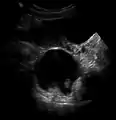

Large ovarian cyst

Dermoid cyst in vaginal ultrasonography

A complex cyst due to a dermoid as seen on ultrasound